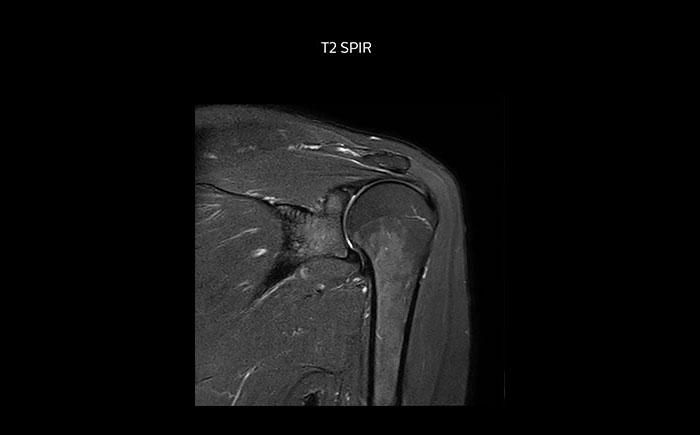

Die Prodiva Schulterspule ist sehr flexibel und hat eine große Abdeckung; dies erleichtert eine gute Positionierung, was wiederum zur ausgezeichneten Bildqualität und hohem SNR beiträgt, die wir in unseren Schulteruntersuchungen erreichen.

Scandauer: 2:55 Minuten, FOV: 160 mm, erfasste Voxel: 0,55 x 0,83 x 3,0 mm.

Scandauer: 04:19 Minuten, FOV: 160 mm, erfasste Voxel: 0,55 x 0,80 x 3,0 mm.

Scandauer: 02:50 Minuten, FOV: 160 mm, erfasste Voxel: 0,70 x 0,99 x 3,0 mm.